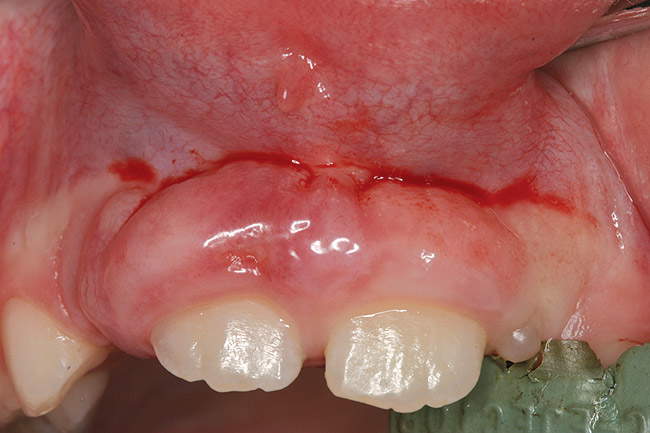

Finally, it must be noted that the psychological and emotional impact of gingival overgrowth receives no or little attention. As increasing numbers of pediatric patients are affected by systemic disease-associated gingival overgrowth, concern should be shown for how pediatric patients interpret what is happening to them and how affected children manage difficulties associated with facial appearance (Figure 1 through Figure 4).

Facial differences can bring stigma upon children and adolescents, affect their psychosocial development, self-esteem, and quality of life.35 Because of the centrality of the face, the mouth, and a smile in human interactions, the effect of gingival overgrowth on the smiles of thousands of children cannot be minimized. Regrettably, the media and public culture place a huge value on physical appearance, which can result in a lack of opportunity for and acceptance of those who look different.36 Reports of perception of physical appearance and social alienation suggest that children with facial differences undergo serious psychological and emotional problems as a result of the feelings of isolation and powerlessness.37 Because gingival overgrowth is a visible facial feature it can be categorized as a facial difference. Therefore, by extrapolation, the studies cited35-37 support that human relationships and interaction are negatively influenced by the appearance of gingival overgrowth. Life can be only the sum of moments, and moments lost to pain and suffering that are psychological or social in nature can mean as much or more than moments lost to physical pain and suffering.

Figure 2  Heart transplant-associated gingival enlargement in a 16-year-old girl. Palatal view.

Figure 2